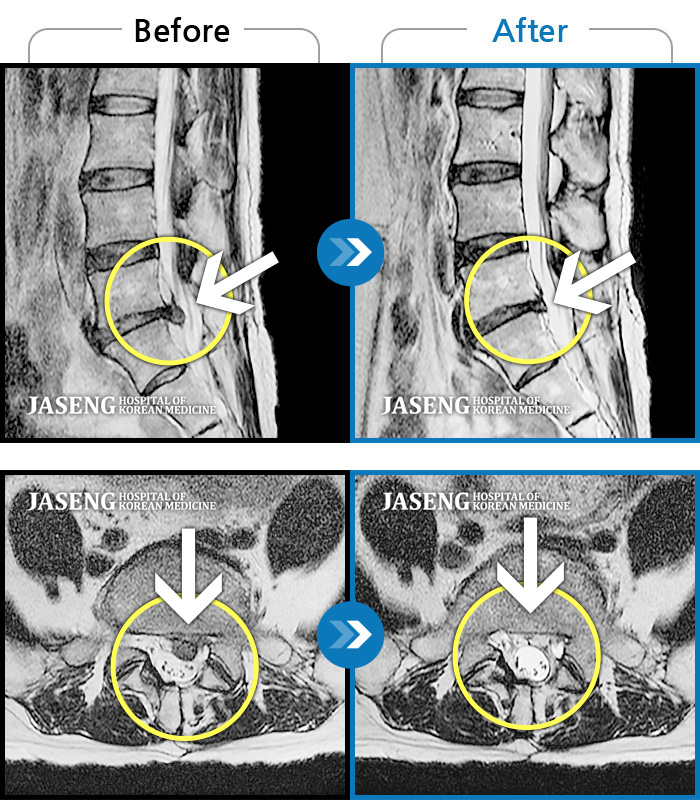

목디스크

도움받은 사례

인천 · 강아현 원장

처음 내원시 목에서 등으로 이어지는 통증 및 우측 팔 저림 증상이 심했고, 약간의 근력저하도 동반되어 일상생활이 어려운 상태였습니다.

촬영시기

2024.04.06 ~ 2024.11.16

2024.11.22